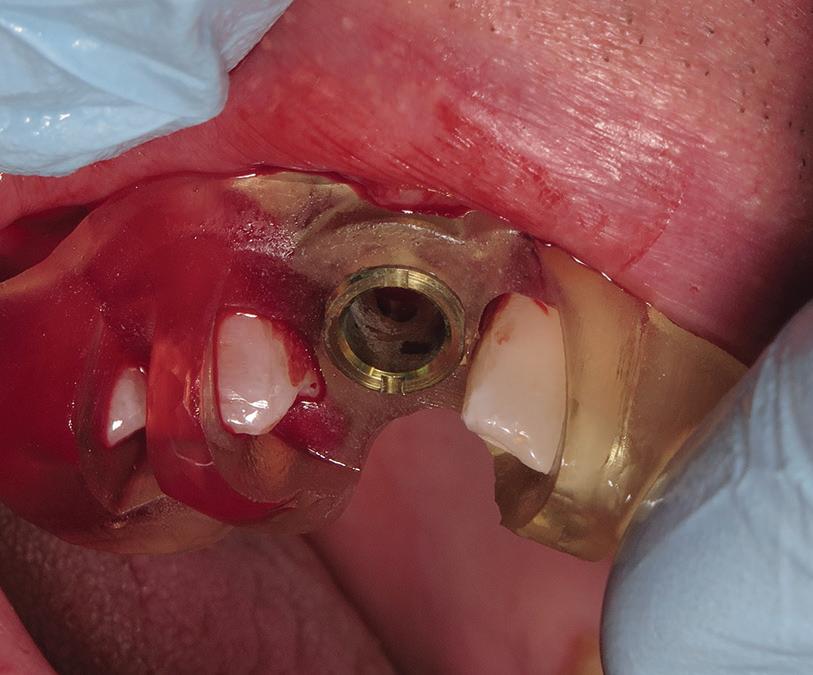

After antiseptic procedures, the surgical site is evaluated. In Fig 4, the site shows good hard and soft tissue volume consistent with that seen in the preoperative planning scans.

The flap design for implant cases usually extends to half a tooth beyond the surgical site in each direction. For example, for an implant at site 19, the flap is extended to the mesiofacial surfaces of teeth 18 and 20. It is also reflected at least 2 mm buccally and lingually to allow full visualization of the bone at the surgical site. The flap is raised with a Woodson elevator or a Molt No. 9 elevator, and the surgical site is examined (Fig 5). The surgical guide is tried on to ensure there are no issues with the fit or positioning of the guide (Fig 6). One benefit of using a surgical guide is that it holds the flap out of the way once it is

fully seated, freeing up the dentist’s or assistant’s hand.

Fig 5. The reflected flap reveals bleeding vital bone and maintenance of ridge width.

Fig 4. The fully healed site is ready for implant placement.

Fig 6. The seated guide reveals an intimate fit with the dentition.